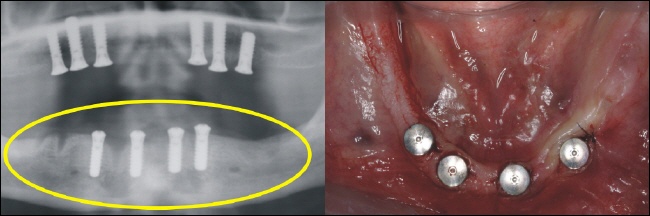

Im Unterkiefer können die vier Implantate (Standardversorgung) im vorderen Kieferbereich eingebracht werden (gelber Kreis im Röntgenbild). |